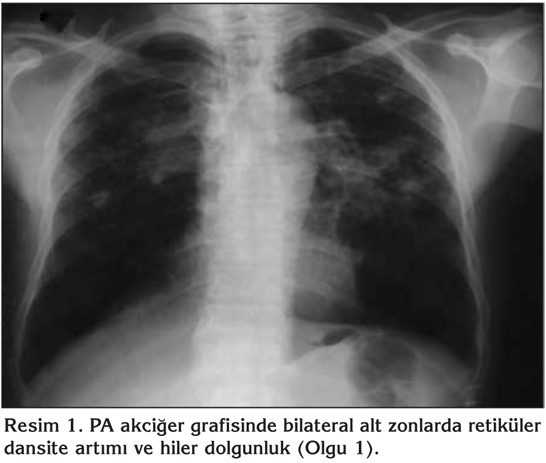

Altm?? alt? ya??nda erkek hasta, nefes darl???, ?ks?r?k, balgam ve hemoptizi ?ikayetleriyle ba?vurdu. K?rk be? paket/y?l sigara kullanma ve k?m?r madeni i??ili?i ?yk?s? olan hastada ayr?ca KOAH, hipertansiyon ve kalp yetmezli?i mevcuttu. Daha ?nce ?ekilmi? olan posteroanterior (PA) akci?er grafisinde bilateral alt zonlarda retik?ler dansite art?m? ve hiler dolgunluk tespit edilen hastan?n hemoptizi ?ikayetinin olmas? ?zerine pn?mokonyoz, KOAH ve akci?er kanseri ?n tan?lar?yla yat?r?larak toraks BT planland? (Resim 1). Hastadan rutin tetkiklerinin yan? s?ra ?? kez balgam aside diren?li basil (ARB) ve balgam sitolojileri istendi. ?stenilen tetkiklerin sonu?lar? normal olarak de?erlendirilen hastan?n ?ekilen toraks BT'sinde mediastinal ve hiler lenfadenopatiler, sol akci?er hilusunda arkus aortayla yak?n ili?kili ve sol ana pulmoner arteri ?epe?evre saran spik?le konturlu yakla??k 3 cm ?apl? kitle saptanmas? ve daha ?nce ?ekilmi? olan radyolojik incelemelerin bulunmamas? ?zerine PET/BT yap?ld? (Resim 2). PET/BT'de sa? alt paratrakeal (SUV max: 8.4), prevask?ler (SUV max: 9.5), subkarinal (SUV max: 11) lenf nodlar?nda ve her iki ana bron? ?evresinde izlenen yumu?ak doku yap?lanmas?nda patolojik artm?? 18F-FDG tutulumlar? izlendi (SUV max: 13.6) (Resim 3,4). Hastada maligniteyi d??lamak amac?yla yap?lan fiberoptik bronkoskopi ile al?nan materyallerin patolojik incelemesi benign olarak geldi. Bronkoskopik incelemeleriyle kesin olarak patolojik tan? konulamayan hastaya maligniteyi d??lamak a??s?ndan mediastinoskopi planland?. Al?nan biyopsi ?rnekleri benign nat?rde gelmesi ?zerine hastan?n meslek ?yk?s?, toraks BT'de pn?mokonyozu d???nd?ren nod?ler lezyonlar? ve lenfadenopatileri olmas?, yap?lan giri?imsel tetkiklerin normal gelmesi, PET/BT'de her iki akci?erde benzer tutulumlar?n olmas? ve hemoptizinin tekrarlamamas? nedeniyle malignite d??lanarak hasta takibe al?nd?.

Resim 1